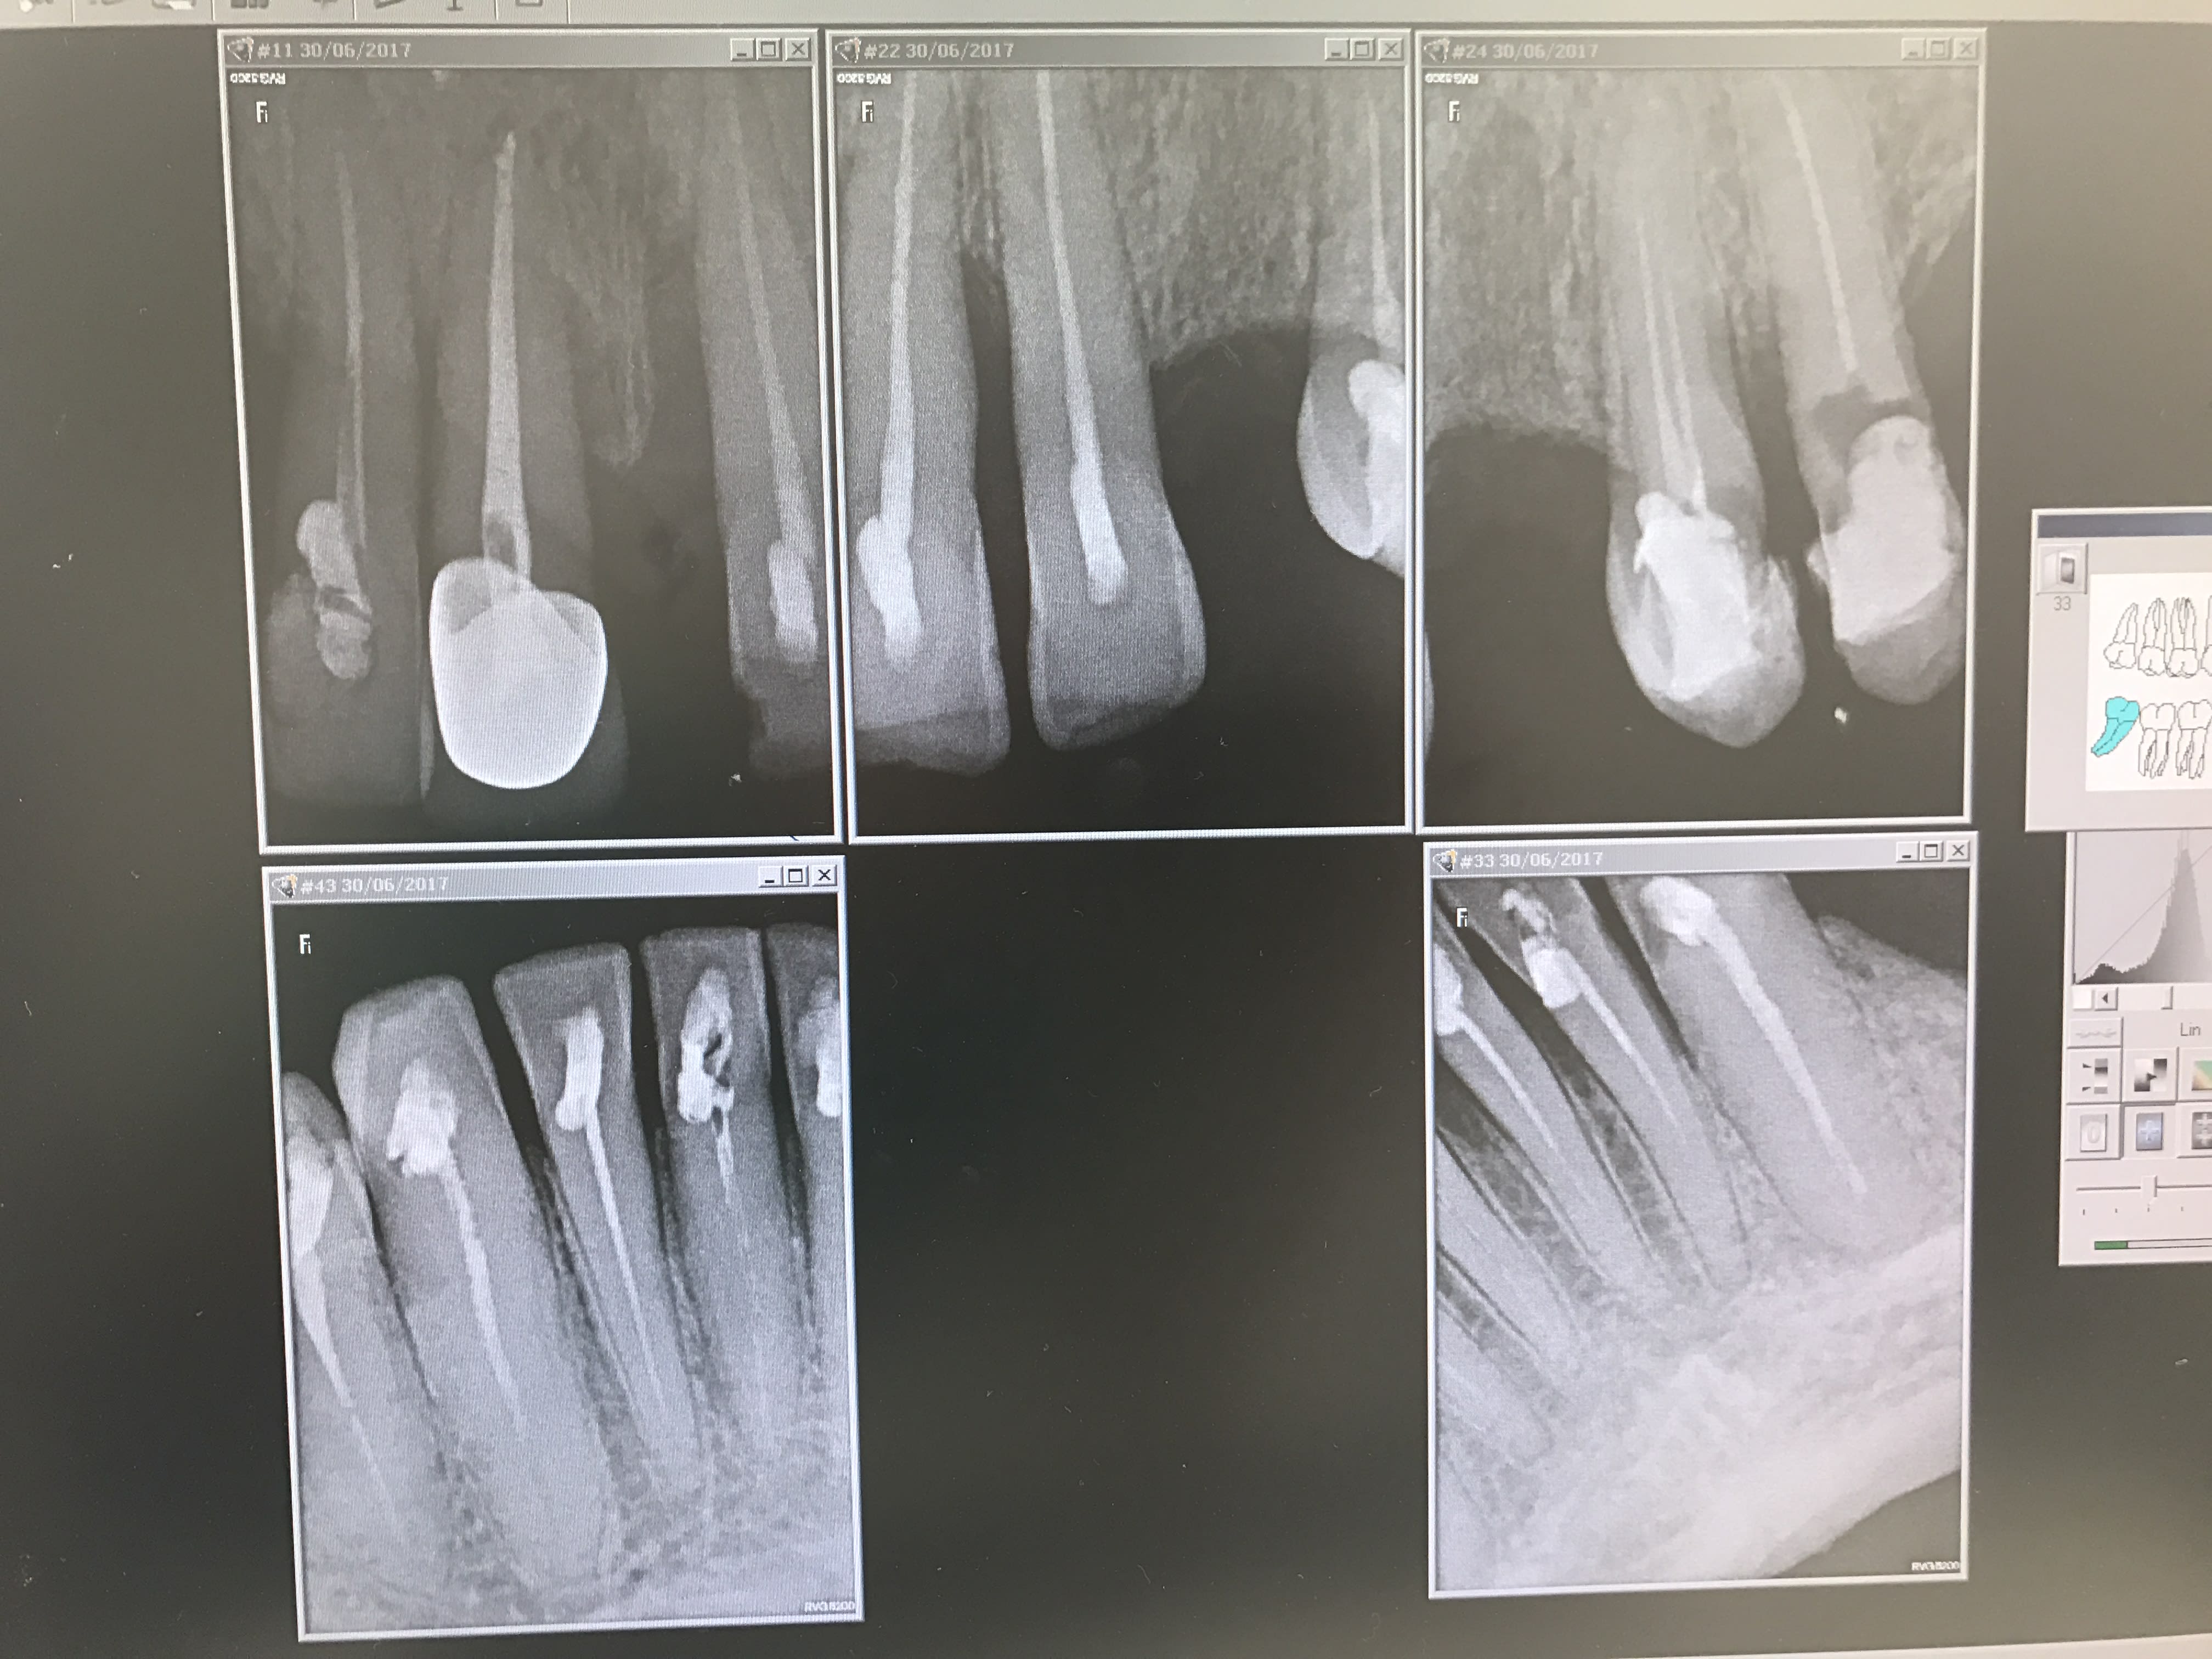

Un nouveau patient (CMU) est venu me voir pour remplacer les dents manquantes.

Il a commencé à se "soigner" chez un confrère mais n'est pas convaincu de ses compétences, tu m'étonnes....

Je le récupère comme ça, pour le moment j'ai dit qu'il allait y avoir du travail sans donner de précision...

Que feriez-vous?

Triste cas de mutilation volontaire ;o((((

Bin tu vois bien le pauvre a eu pile poil des caries en forme de cavité d'accès -_-.